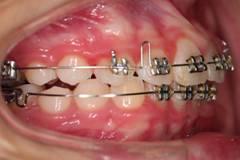

早期矯正中